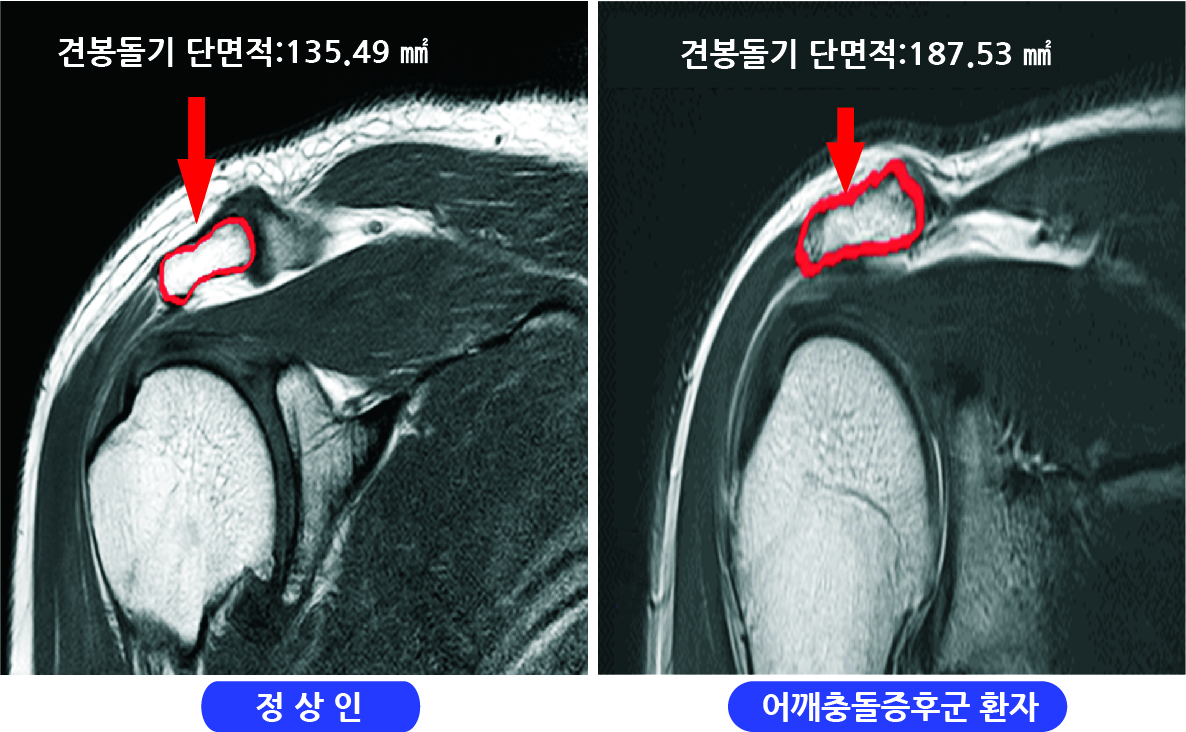

Q=어머니는 오랫동안 어깨를 앓고 있었지만, 얼마 전부터 잠자리에서도 어깨 통증에 시달리고 있습니다. 팔도 거두는 것이 큰일이라고 합니다. A=흔히 있는 어깨의 질환으로 충돌 증후군(회전 근개 손상)오십견(유착성 관절 피막염), 석회화 건염, 관절 와진 파열, 근막 통증 증후군 등이 있고 외에도 목과 어깨의 다양한 부위의 신경 압박으로 어깨의 통증이 있습니다. 많은 환자들이 이렇게 말하고 있습니다. “여러 병원·의원에서 뢴트겐(X선)을 찍고 이상이 없는 주사를 맞아 물리 치료를 했지만 별로 효과가 없어 그 때만 증세가 더 심해지는 것 같아요.”X선에서는 뼈 이외의 무수한 구조물을 볼 수 없습니다. 골절에 의한 어깨 통증 외에 엑스 레이로 보이는 어깨 통증의 원인은 골암와 석회화 건염 뿐입니다. 그러므로 외상이 없을 때는 X선 검사는 필요 없다고 생각합니다. 많은 분들이 장기간 충돌 증후군의 치열한 인대 손상을 주사와 물리 치료에만 의존했으나 수술 시기를 놓쳐서 심한 관절염으로 팔을 쓰지 못한다 아쉬운 경우를 자주 봅니다. 어깨의 회전통과 활막이 어깨 관절을 안정시키는 유일한 구조물입니다. 그래서, 인대 손상과 어깨의 회전통이 심한 위축이 오면 어깨 관절이 불안정해지면서 장기적으로 치열한 관절염에 진행되고 팔을 못쓰게 될 뿐 아니라, 아파서 잘 수 없게 됩니다. 진찰시에 충돌 증후군이 의심스러우면 꼭 자기 공명 영상(MRI)검사를 해야 합니다. MRI영상으로 힘줄 손상 정도로 근육의 퇴화 정도를 보며 수술 여부를 정합니다. 그래서 미국의 상당수 주에서 MRI검사 없이는 관절경 수술을 금지하고 있습니다. -영상 의학과 의원(소죠은데 원장)-

Q=어머니는 오랫동안 어깨를 다치셨지만, 얼마 전부터는 잠자리에서도 어깨 통증으로 고생하고 계십니다. 팔도 올리기 힘들대요. A=흔히 흔한 어깨질환으로 충돌증후군(회전근개손상), 오십견(유착성관절막염), 석회화건염, 관절와순파열, 근막통증후군 등이 있으며 이외에도 경추나 어깨 여러 부위의 신경압박에 의한 어깨통증이 있습니다. 많은 환자들이 이렇게 말합니다. 여러 병의원에서 엑스레이(X-ray)를 찍고 이상이 없어 주사를 맞고 물리치료를 했는데 별 효과가 없고 그때만 증상이 더 심해지는 것 같아요. 엑스레이에서는 뼈 이외의 무수한 구조물을 볼 수 없습니다. 골절에 의한 견통 외에도 엑스레이에서 볼 수 있는 견통의 원인은 골암과 석회화 건염뿐입니다. 그렇기 때문에 외상이 없을 때는 엑스레이 검사는 필요 없다고 생각합니다. 많은 분들이 장기간 충돌증후군으로 인한 극심한 인대 손상을 주사와 물리치료에만 의존하다가 수술 시기를 놓쳐 심한 관절염으로 팔을 사용할 수 없게 되는 안타까운 경우를 자주 봅니다. 어깨 회전근과 활막이 견관절을 안정시키는 유일한 구조물입니다. 따라서 인대 손상과 어깨 회전근의 심한 위축이 오게 되면 견관절이 불안정해지고 장기적으로 심한 관절염으로 진행되어 팔을 사용하지 못하게 될 뿐만 아니라 아프고 잠을 잘 수 없게 됩니다. 진찰 시 충돌증후군이 의심되면 반드시 자기공명영상장치(MRI) 검사를 해야 합니다. MRI 영상에서 힘줄 손상 정도와 근육 퇴화 정도를 보고 수술 여부를 결정합니다. 따라서 미국의 많은 주에서 MRI 검사 없이는 관절경이나 수술을 금지하고 있습니다. – 영상의학과의원(서정대원장)-